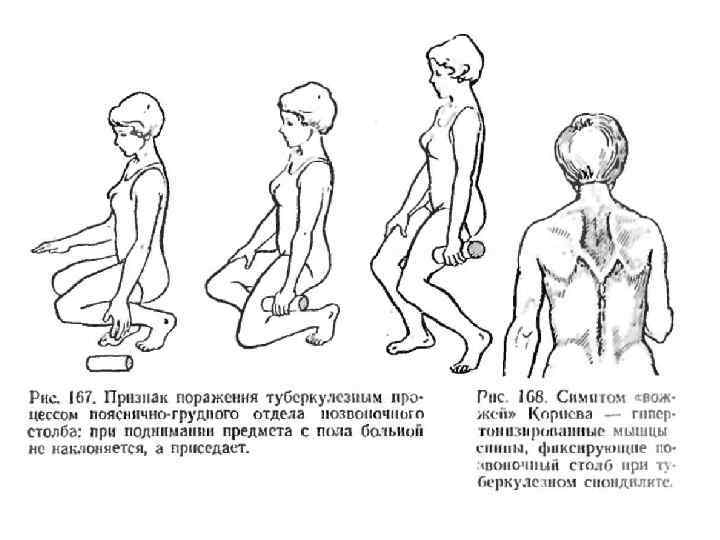

Спондилолитическая фаза • Спондилолитическая фаза (разрушение тела позвонка и переход процесса на межпозвонковые диски и окружающие мягкие ткани). • Кроме общих симптомов характеризуется появлением болей при наклоне туловища и ограничение движений из-за болей в позвоночнике. • При осмотре определяется искривление линии позвоночного столба, выступание остистого отростка, горб. • Для этой фазы характерен также "симптом вожжей" - напряжение мышц спины в виде тяжей, идущих от углов лопаток к поражённому позвонку. При надавливании на остистый отросток разрушенного позвонка пациент ощущает боль. • На спондилолитическом этапе туберкулёза позвоночника появляются натёчные абсцессы и свищи. Смещение тел позвонков может привести к сдавлению спинного мозга и развитию параличей конечностей, нарушениям функций тазовых органов. • На рентгенограмме определяется деструкция тел позвонков - признак патологического компрессионного перелома позвоночника, тени натёчных абсцессов.

Спондилолитическая фаза • Спондилолитическая фаза (разрушение тела позвонка и переход процесса на межпозвонковые диски и окружающие мягкие ткани). • Кроме общих симптомов характеризуется появлением болей при наклоне туловища и ограничение движений из-за болей в позвоночнике. • При осмотре определяется искривление линии позвоночного столба, выступание остистого отростка, горб. • Для этой фазы характерен также "симптом вожжей" - напряжение мышц спины в виде тяжей, идущих от углов лопаток к поражённому позвонку. При надавливании на остистый отросток разрушенного позвонка пациент ощущает боль. • На спондилолитическом этапе туберкулёза позвоночника появляются натёчные абсцессы и свищи. Смещение тел позвонков может привести к сдавлению спинного мозга и развитию параличей конечностей, нарушениям функций тазовых органов. • На рентгенограмме определяется деструкция тел позвонков - признак патологического компрессионного перелома позвоночника, тени натёчных абсцессов.

Туберкулез позвоночника • Постспондилолитическая фаза характеризуется стиханием воспаления. Однако натёчные абсцессы, свищи и нарушения иннервации сохраняются.

Туберкулез позвоночника • Постспондилолитическая фаза характеризуется стиханием воспаления. Однако натёчные абсцессы, свищи и нарушения иннервации сохраняются.